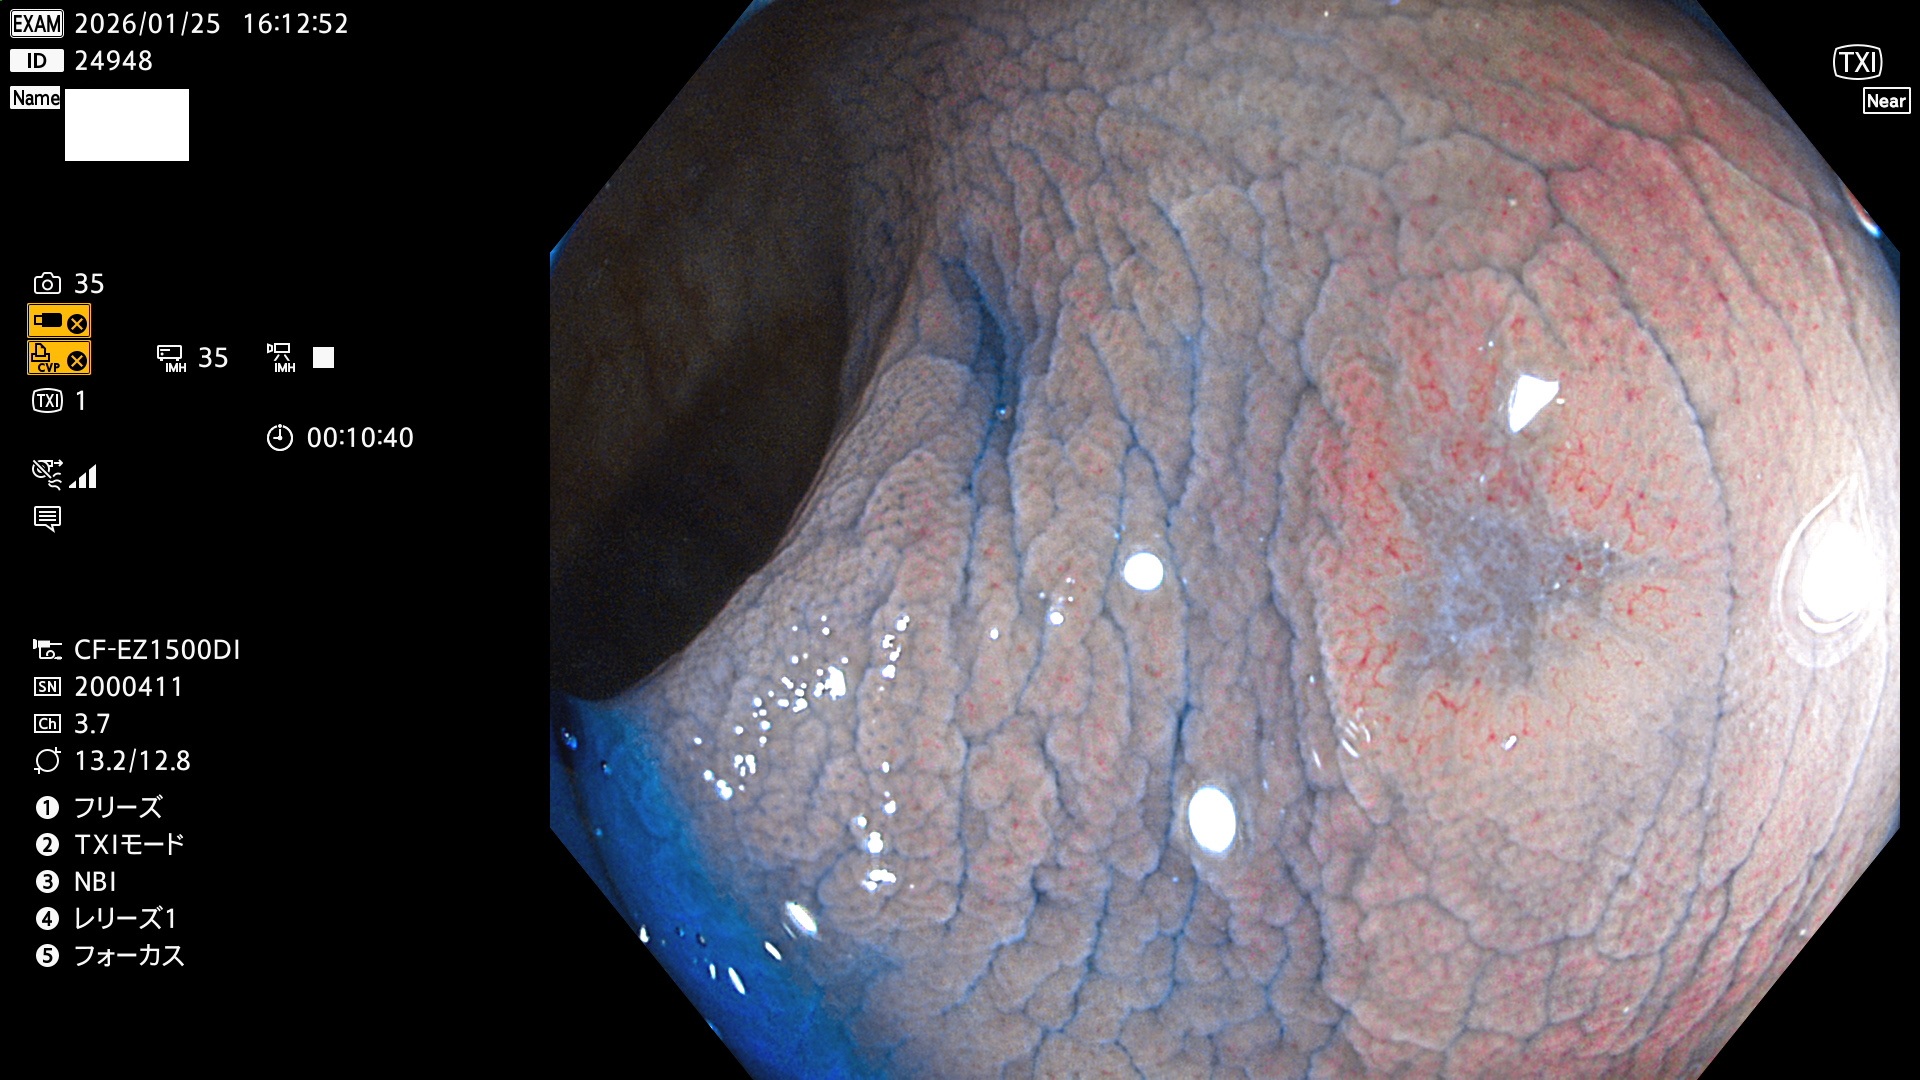

完全に平坦な物をUb、陥凹している物をUcと呼びます。Ubは認識が困難で、Ucはびらん(炎症)と紛らわしいために見落とされやすく、「内視鏡後・大腸癌」の原因になります。

専門的)Uc=De Novo癌? 内視鏡の解像度が低かった時代、このような説もありました。しかし今日の高精度内視鏡では良性の微小なUc型腺腫(APC遺伝子異常の腺腫)が日常的に見つかります。Ucこそが多段階発癌(Adenoma-Carcinoma Sequence)のMain Routeです。

毎週の検査(木・金・土・日)に発見されたUbとUc型・腺腫を、その週の日曜の夜にUPし1週間、提示します。

2026年1月22日〜1月25日の4日間(35件)4個 (Uc_ADR=4個/32人=13%)